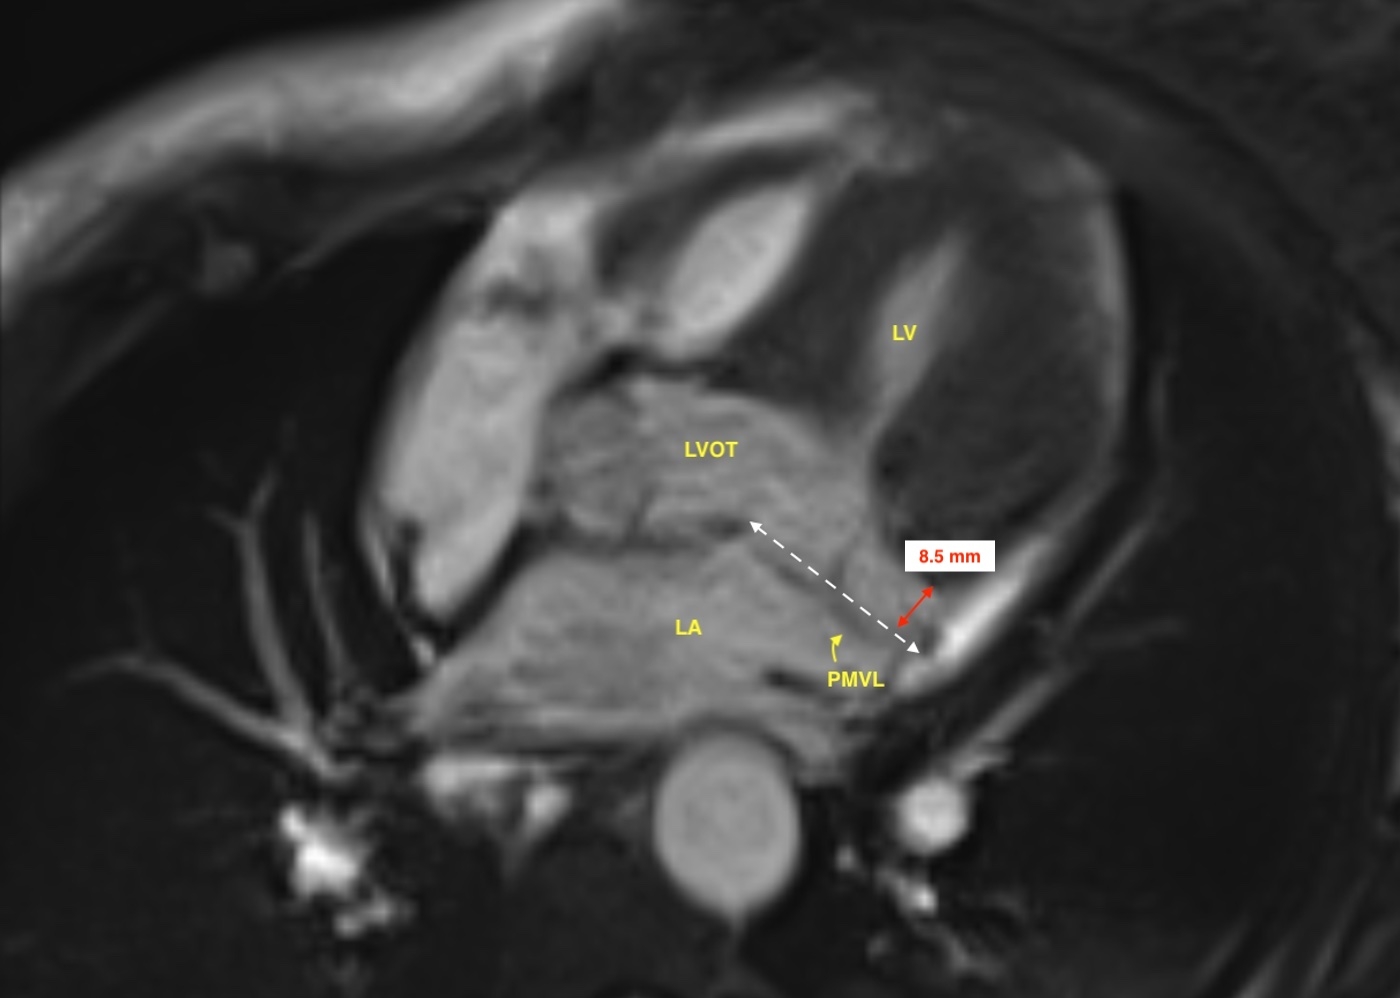

Following stabilization, the patient’s LVEF recovered, and she was successfully decannulated from ECMO. Repeat CMR prior to discharge confirmed bileaflet mitral valve prolapse with MAD measuring 8.5 mm in length (Figure 2). She was transitioned to oral antiarrhythmic therapy and underwent subcutaneous implantable cardioverter-defibrillator (ICD) placement. Outpatient genetic testing was negative.

MAD is a recognized substrate for out-of-hospital cardiac arrest. In this patient, the presence of MAD, along with a catecholamine surge from a ruptured ectopic pregnancy and acute hypokalemia from vomiting, likely created a highly proarrhythmic state. High-risk features in MAD associated with arrhythmic events include bileaflet mitral valve prolapse, myocardial fibrosis on CMR, MAD length equal to or >8.5 mm, and peak lateral mid-systolic velocity >16 cm/s. ICD implantation should be considered in patients with these characteristics, particularly those with sustained ventricular arrhythmias.